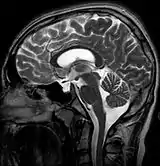

| MRI of Empty Sella | |

Empty sella syndrome is the condition when the pituitary gland shrinks or becomes flattened, filling the sella turcica with cerebrospinal fluid instead of the normal pituitary.[2] It can be discovered as part of the diagnostic workup of pituitary disorders, or as an incidental finding when imaging the brain.[1]